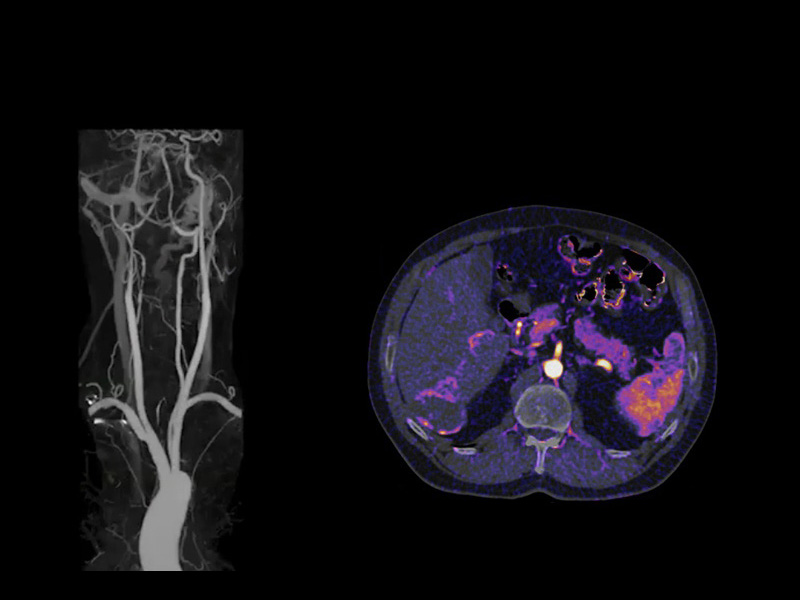

SURESubtraction CT

In CTA examinations Angiography SURESubtraction CT (SCT) has the ability to remove bone, calcium and stents from data sets allowing clinicians an unobstructed view of the arteries.

Moreover, SURESubtraction can create iodine mapping SURESubtraction CT (SCT) to enable the assessment of the distribution of contrast media within the body to visualize local perfusion.

SURESubtraction SCT has protocol integrated automation at every step to empower even a novice operator with the skills to perform brilliantly the first time — every time.

Prior to subtraction, Canon Medical Systems' deformable registration allows pixel matching between the pre-contrast and contrast enhanced data for precise digital subtraction and iodine mapping, saving time and improving diagnostic accuracy.